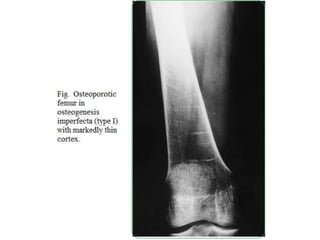

Osteoporosis occurs with cortical thinning with

bowed thin gracile long bones.

OI Diagnosis-Plane radiography

32

Obtain a radiographic skeletal survey after birth.

Generalized osteoporosis is present

In milder forms (Types I & IV)–Thin and gracile bones

Osteogenesis imperfecta. Results from genetic

mutations causing abnormalities in Type I collagen, and

resulting in osteoporosis and low-trauma fractures

(brittle bone disease). The different types vary in clinical

presentation and severity.

Frontal view of the femora in an infant showing reduced

bone density and marked deformity due to multiple